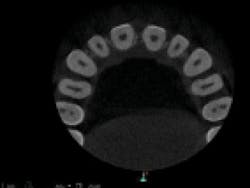

Figures 4–8: Apical lesion on tooth No. 9 is confirmed on all 3-D views

I examined a patient who had experienced trauma to his two front teeth approximately five years prior and was now experiencing occasional pain. From an x-ray, the problem could not be diagnosed as definitive (figure 3). However, as soon as I took the 3-D image, I could see an abscess, which required a root canal (figures 4–8).